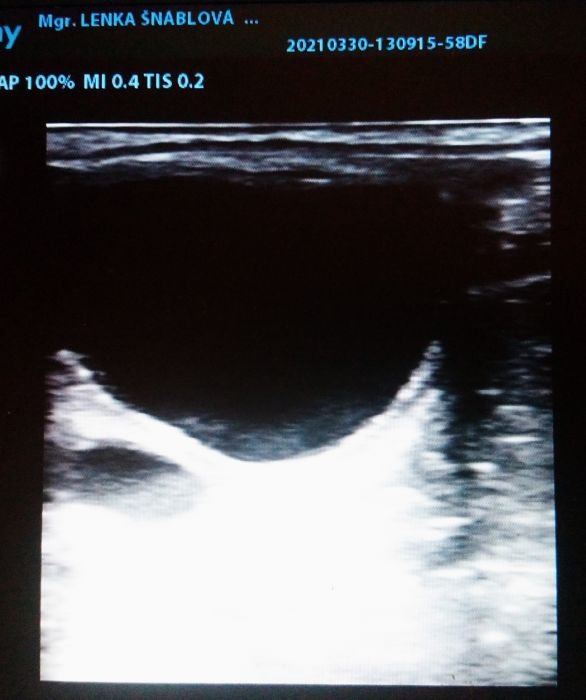

Folikulární vlna na vaječníku klisny

Chovná klisna by měla být pravidelně očkována dle vakcinačního schématu, aby se snížilo riziko případného abortu. Před připouštěním je třeba brát v potaz i roční období. V zimě je valná většina klisen v anestru, tedy v období, kdy na vaječnících nedozrávají folikuly, klisna necykluje. V jarním přechodném období začínají klisny cyklovat (únor/ březen), zpočátku folikuly atretizují – neovulují. Pro chov je také důležité zvážit, zda narozenému hříběti budou poskytnuty veškeré podmínky pro správný vývoj – kvalitní výživa, dostatek prostoru k pohybu, sociální kontakt s vrstevníky.